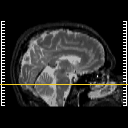

MR Study #19, August 25, 1991 -- Slice #13

[Home][Help][Clinical][Tour 1][Tour 2] Slice 13